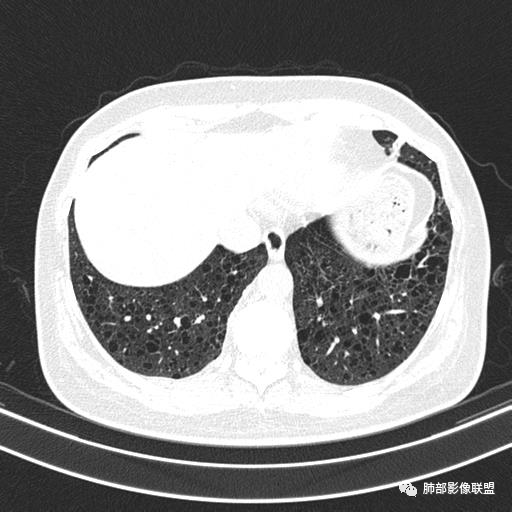

女,46,活动性气喘1年。苯吸入史半年。胸部CT:两肺弥漫囊腔,上至肺尖,下至肋膈角,形态类似小囊腔。考虑:LAM,鉴别LIP,BHD,PLCH等。

双肺弥漫大小不一薄壁含气囊腔,囊间肺组织正常,正常肺背景,肺尖肺底受累;青年女性,气喘,支持LAM

CT表现:双肺弥漫大小不等的薄壁囊腔,囊壁<2mm,外形规则,血管影多位于囊腔周围,囊腔之间肺组织正常,随着疾病进展到晚期,囊腔变大、增多,不可胜数,囊腔可融合成较大的囊,与肺气肿相似,形成间质性肺纤维化。部分病例可出现结节影。

1.小叶中心性肺气肿:上肺为主,无壁,中央见小血管影,位于小叶核心周围,部分血管可推移到边缘,周围肺组织正常